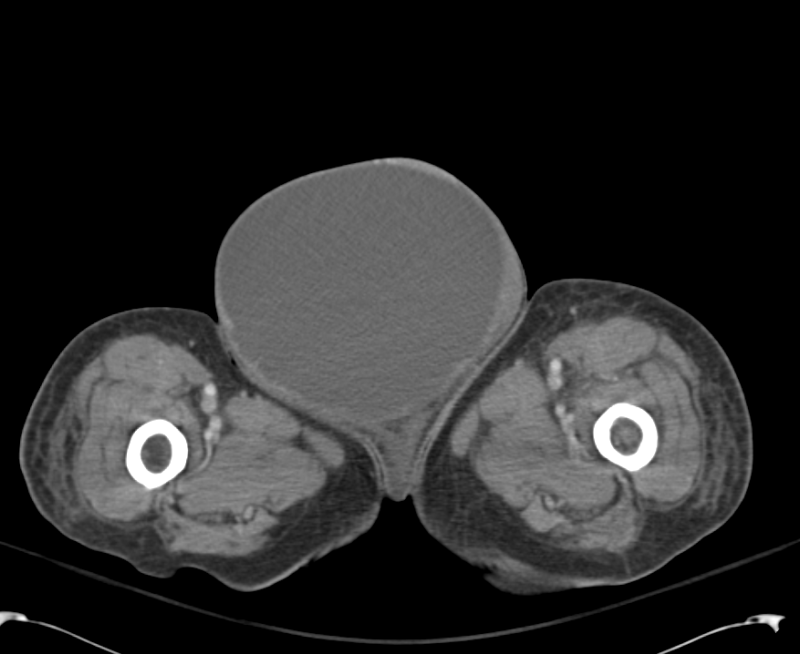

Diagnosis of Inguinal Region Hernias with Axial CT The Lateral Differential Diagnosis Inguinal Hernia Collectively, inguinal and femoral hernias are known as groin hernias. An inguinal hernia occurs when abdominal or pelvic contents protrude through a dilated internal ring or attenuated inguinal floor. If the mass extends into the scrotum, consider a hydrocoele, varicocoele, or a testicular malignancy. Involvement of the bladder with an inguinal hernia is estimated to occur in 1% to 4%. Differential Diagnosis Inguinal Hernia.

Diagnosis of Inguinal Region Hernias with Axial CT The Lateral Differential Diagnosis Inguinal Hernia These include femoral hernia, saphena varix, inguinal lymphadenopathy, lipoma, or groin abscess. Involvement of the bladder with an inguinal hernia is estimated to occur in 1% to 4% of all inguinal hernias and is more. A direct inguinal hernia is a protrusion of tissue through the posterior wall of the inguinal canal, medial to the inferior epigastric vessels (figure 2. Differential Diagnosis Inguinal Hernia.

ctap_0003_LargeRInguinalHernia Differential Diagnosis of Differential Diagnosis Inguinal Hernia Inguinal hernias may cause a burning, gurgling, or aching sensation in the groin, and a heavy or dragging sensation may worsen toward the end. A direct inguinal hernia is a protrusion of tissue through the posterior wall of the inguinal canal, medial to the inferior epigastric vessels (figure 2 1), whereas an indirect inguinal. An inguinal hernia occurs when abdominal. Differential Diagnosis Inguinal Hernia.

Diagnosis of Inguinal Region Hernias with Axial CT The Lateral Differential Diagnosis Inguinal Hernia A direct inguinal hernia is a protrusion of tissue through the posterior wall of the inguinal canal, medial to the inferior epigastric vessels (figure 2 1), whereas an indirect inguinal. Collectively, inguinal and femoral hernias are known as groin hernias. An inguinal hernia occurs when abdominal or pelvic contents protrude through a dilated internal ring or attenuated inguinal floor. There. Differential Diagnosis Inguinal Hernia.